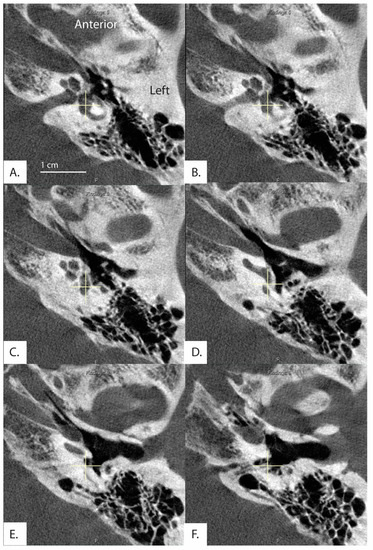

2D Measurements of the Angle of the Vestibular Aqueduct Using CT Imaging

by Diane Jung, Nimesh Nagururu, Ferdinand Hui, Monica S. Pearl, John P. Carey and Bryan K. Ward

Recently, Bächinger et al. developed a software that measures the angle between the vestibular aqueduct proximal to the vestibule and the distal vestibular aqueduct on computed tomography (CT) scans and found differences in the vestibular aqueduct angle between the hypoplastic and degenerative categories [...] Read more.

Recently, Bächinger et al. developed a software that measures the angle between the vestibular aqueduct proximal to the vestibule and the distal vestibular aqueduct on computed tomography (CT) scans and found differences in the vestibular aqueduct angle between the hypoplastic and degenerative categories of Meniere’s disease (MD). Hypoplastic radiological findings were associated with the development of bilateral MD and hypoplastic changes were not found outside of fetal temporal bones and individuals with MD. The purpose of this study is to examine how the software developed by Bächinger et al. performs when applied to a large dataset of adult patients with varied otologic diagnoses. Adult patients who underwent high resolution flat panel CT scans without intravenous contrast (n = 301) were retrospectively reviewed. Measurements of the angle of the vestibular aqueduct were made using the previously developed software tool. The tool could be applied to measure the vestibular aqueduct angle in most CT scans of the temporal bones (n = 572 ears, 95%). While the majority of ears fell within the normal range of <120 degrees (n = 462, 80%), fourteen ears (2.3%) in 13 patients were found to have vestibular aqueduct angles that meet criteria for hypoplastic MD (>140 degrees). Only one of the 13 patients had a diagnosis of MD and not in the ear in the hypoplastic category. An inconsistent pattern of other otologic diagnoses were found among the 13 individuals meeting criteria for hypoplastic MD. Although prior reports indicate the software has prognostic value in individuals with MD, these results suggest that the software may have lower positive predictive value when applied to a large population of individuals with varied otologic diagnoses. Full article